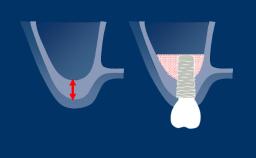

Complications that are associated with the surrounding peri-implant mucosa or bone are referred to as biological complications. They occur when there is an imbalance between the bacterial biofilm challenge to the tissues around an implant and the host defense, resulting in an inflammatory process.

The biological complications addressed in this module are the peri-implant diseases referred to as peri-implant mucositis and peri-implantitis, both of which may occur around osseointegrated implants.